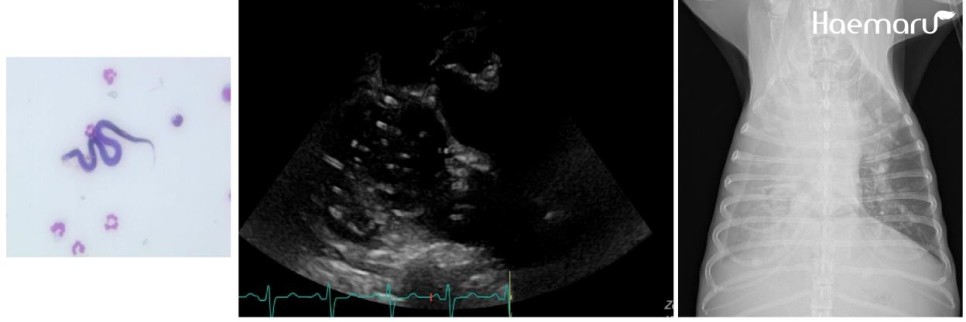

검사상 심장사상충 감염이 확인되어 사상충에 의한 폐고혈압과 우심부전, 이로 인한 흉수 및 복수 발생이 의심되는 상황이었습니다.

마이크로filaria, 우심내 심장사상충, 방사선상의 흉수 소견

입원 처치 후 폐야 개선 소견 확인